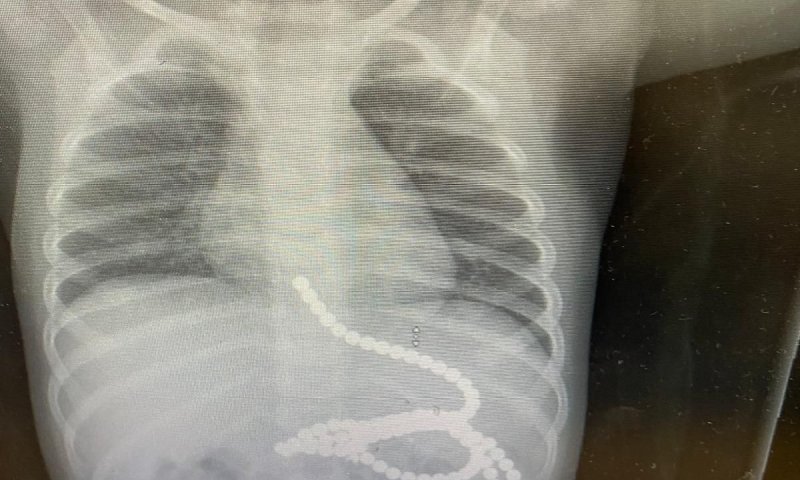

עם הגעתו, בוצע צילום רנטגן, בו נראתה כמות גדולה של מגנטים בקיבה ובאזור הוושט. בעקבות זאת עבר הפעוט אנדוסקופיה, במהלכה נשלפו מרבית המגנטים מגופו. הפעולה בוצעה ע"י ד"ר אורית אלקיים, גסטרו-אנטרולוגית ילדים ורופאה בכירה באגף ילדים, בשיתוף עם צוות גסטרו-אנטרולוגיה מבוגרים שבהובלת ד"ר ויסאם סבית וד"ר אמיר שאהין.

עקב השהות הממושכת של המגנטים במערכת העיכול, והיצמדות חלקים מצינור העיכול האחד לשני ע"י המגנטים, חדרו כמה מגנטים את דופן הקיבה, ולא ניתן היה לשלוף אותם מבלי לסכן את חיי הפעוט. בעקבות זאת הוכנס התינוק לניתוח חירום.

ד"ר נדב סלייפר, מנהל המחלקה לכירורגיית ילדים, שניתח את התינוק, סיפר כי בניתוח נמצאו 11 מגנטים נוספים באזורים שונים של צינור העיכול, וכן חורים בקיבה, במעי הדק ובמעי הגס, שנגרמו כתוצאה מחדירת המגנטים את דופן המעי. עם שליפת המגנטים, תוקנו הפגיעות שנוצרו במערכת העיכול.